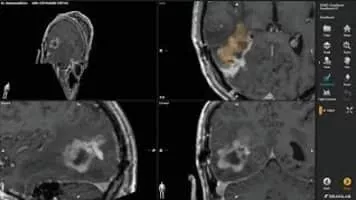

Brainlab is a privately held German medical technology company headquartered in Munich, Bavaria that develops hardware and software for radiosurgery, image guided surgery technologies for neurosurgery, . . .